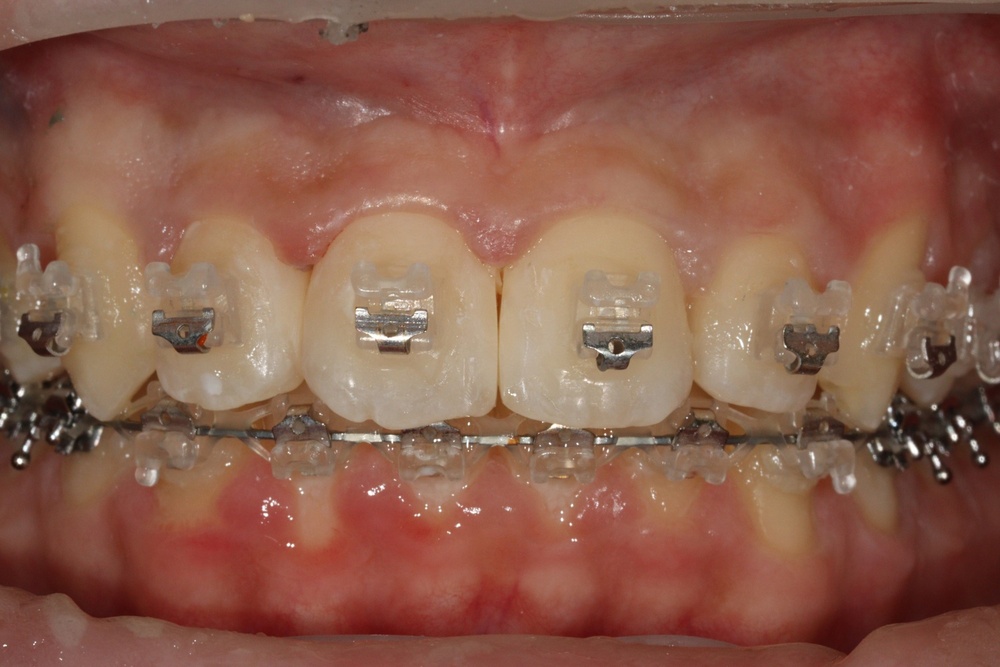

치아 배열이 거의 완성된 상태로 치료 전 말씀드렸던 치아사이의 틈(블랙트라이앵글)이 있습니다.

환자분과 상의 후 위쪽은 벌어진 공간을 레진으로 메꾸기로 하였습니다.

치아가 가지런해졌고, 윗니 치아 사이의 틈도 메꿔졌으며, 치아에 있던 충치도 모두 치료하였습니다.